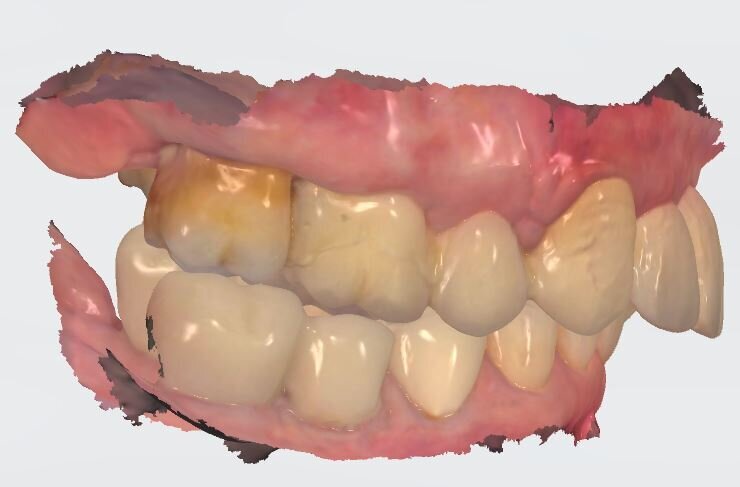

Fig. 5_Impronta digitale in occlusione visione laterale.

Fig. 6_Visione interna del provvisorio eseguito dal wax-up in prematura.